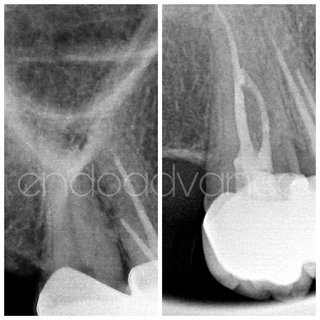

Αρχική ενδοδοντική θεραπεία σε κεντρικό τομέα της άνω γνάθου με δύο ρίζες